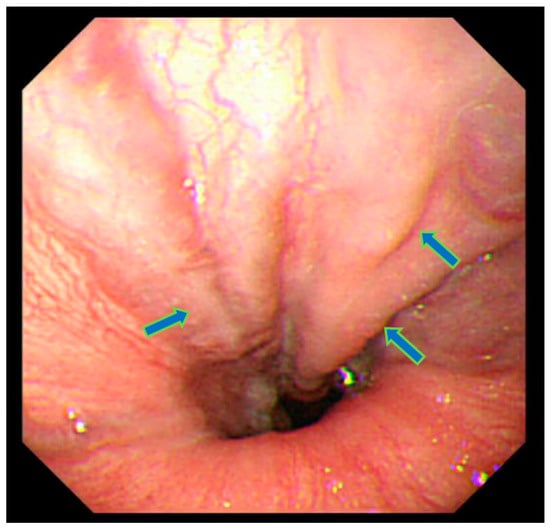

At age 47, the patient experienced stomach discomfort and underwent upper gastrointestinal endoscopy, which incidentally revealed esophageal varices (Figure 1). There was no relationship between the stomach discomfort and the esophageal varices. His height was 155.2 cm (−2.5 SD) and his weight 72.2 kg (body mass index: 29.9 kg/m2). The patient was not married and worked as a computer engineer. He had no family history of diabetes mellitus and no history of a drinking or smoking habit. In a physical examination, there were no cutaneous changes indicating extrahepatic manifestations of palmar erythema or spider angioma. Moreover, dilated superficial abdominal vein and hepatosple nomegaly were not observed at that time.

Figure 1.

Upper gastrointestinal endoscopy showing esophageal varices in the lower esophagus (arrows). Varicose veins have the same color as normal esophageal mucosa. Bleeding or redness on the surface was not recognized. Judged to be grade 1.